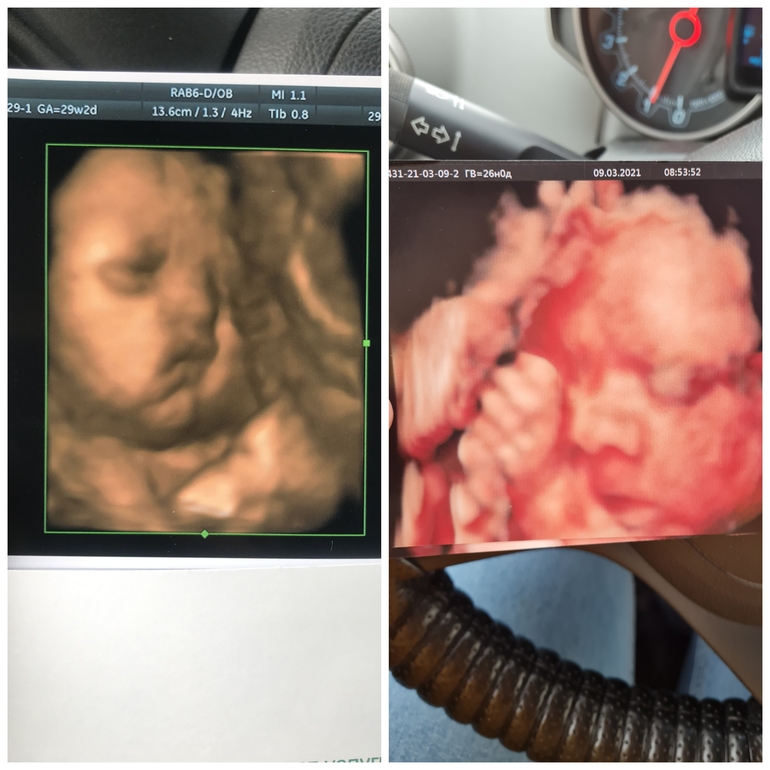

3Д УЗИ в 26 недель, фотопуз)

Вот такая красота получилась😋

По показателям все конфетно 👌🏻

Вод норма, плацента степень зрелости 1, органы без нареканий, кровотоки тоже, шейка абдоминально 36 точно, врач спрашивал смотреть ли вагинально, я отказалась, размер хороший, смысл раздеваться)

Вес сегодня(26 нед ровно) у крошки 945 гр , у Евы в 26 недель тоже ровно был вес 910 гр)